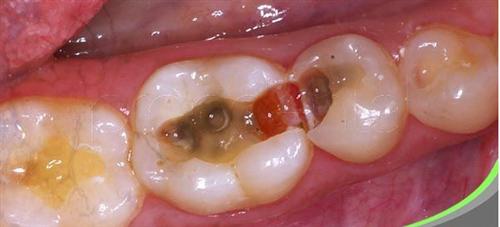

龋齿龋坏的程度怎么分 龋病的形成首先是牙釉质磷灰石晶体的破坏,使得透明而有光泽的釉质变混浊呈现出白垩色斑病变范围逐渐扩大并向深层发展,使牙本质脱钙变软。食物与细菌代谢产生的色素连同牙... 牙齿治疗 朱小溪 1138 2024-03-23

龋病按病变程度怎么分类 龋病是发生在牙体硬组织上慢性、进行性破坏的细菌性疾病。临床表现为牙体硬组织色、形、质各方面发生变化,随着硬组织脱矿和有机物分解的进行,最终牙体组织崩解形成不可自... 牙齿治疗 范姜英杰 914 2024-03-11

龋齿的分类有哪些 按病变深度分类根据病变深度可分为浅龋、中龋和深龋。这一分类方法在临床上最为适用。牙骨质龋多表现为潜掘性龋或表层剥脱,由于牙骨质较薄,尤其是牙颈部,因此病变可很快... 牙齿治疗 吴芳芳 726 2023-11-27